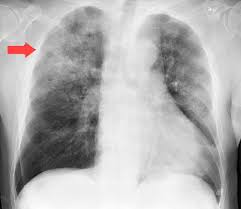

acute inflammation in the lung tissues caused by bacterial, viral, or fungal, infection or chemical irritants

what is pnemonia?

This highly contagious bacteria is carried mucus droplets and is suspended in the air. It affects the lungs as well as spine, brain, and kidneys.

What is TB tuberculosis?